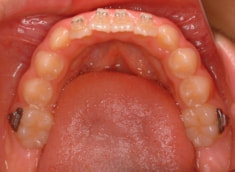

治療開始から3ヶ月後

治療分析:日本人の反対咬合や下顎前突は、上顎の劣成長を伴なうことが多いので、上顎を側方拡大と前方に牽引しました。側方拡大方法は急速拡大で、正中口蓋縫合の拡大を行い、横口蓋縫合を剥がす効果で、前方牽引の効果を促進します。

治療開始して3ヶ月で前歯はジャンプしておりますが、フェイスマスクをこの後もしっかり使用していただくことが大切です。